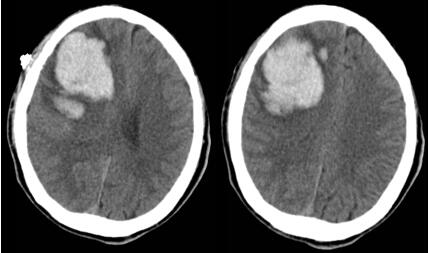

患者王某,男,61岁,入院前突发左侧肢体活动不灵伴意识障碍2小时。查体时显示神志不清,昏迷状态,头颅CT结果显示:右侧基底节区脑出血约40ml。

入院后,在白西民主任、姚胜副主任组织下,党俊涛主任医师及冯毅副主任医师协作,由杜春亮主治医师、王小峰医师及王举医师实施手术。避开重要的血管和神经,取右额平行于中线纵形切口长约4cm,骨窗直径2.5cm,经额叶顺穿刺将套筒准确置入患者大脑深部的血肿腔,建立供内镜通过的微小孔道,再置入圆珠笔芯粗细内镜,以提供良好的照明和视野,很快就准确彻底地清除了深藏脑内的淤血。术后CT显示血肿清除干净,目前患者神志清楚,已康复出院。